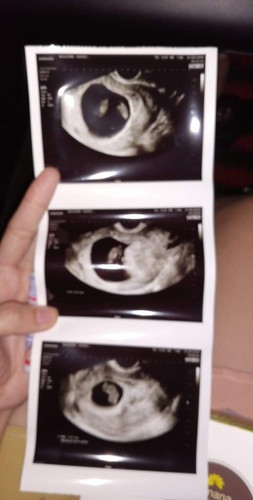

ตืีนนอนตอนเช้าของวันนี้ดิฉันก็ได้เข้าห้องน้ำไปปัสสาวะตามปกติแต่สิ่งที่ไม่ปกติก็คือมีเลือดออกจากช่องคลอดเป็นสีน้ำตาลเข้มเหมือนคนที่คล้ายใกล้จะหายเป็นประจำเดือนแต่ไม่มีความรู้สึกว่าปวดท้อง ก็เลยคิดว่าคงไม่เป็นอะไรสงสัยจะเป็นเลือดล้างหัวเด็ก พอถึงตอนเที่ยงก็ได้เข้าไปปัสสาวะอีกครั้งแต่ไม่พบว่ามีเลือดแล้ว ก็นิ่งนอนใจไม่ได้ติดอะไร ตกมาบ่ายแก่ๆรู้สึกหน่วงๆท้องเวลาเดินก็ได้เอะใจว่ามันไม่ใช่แล้ว รู้สึกกังวนก็เลยไปตรวจที่โรงพยาบาล หมอก็ได้ทำการตรวจภายในก่อนแล้วหมอก็บอกว่า อาการที่มีเลือดออกตามช่องคลอดคือเป็นอาการ ของมดลูกอักเสบ เดี๋ยวเชิญคุณแม่ไปห้องอัลตราซาวนด์น่ะคับ คือตอนนี้เราท้องได้9w1dแล้วค่ะหมอก็ทำการอัลตราซาวนด์บอกว่าคุณแม่ได้ลูกแฝดน่ะ น้ำหนัก1.9กรัม ความยาว1.7เซน หมอก็พูดต่อไปว่าอันนี้มดลูกน่ะครับ อันนี้เป็นถุงน้ำคร้ำปกติ เราก็ยิ้มดีใจมากๆที่ได้ลูกแฝด แต่...ไม่ได้ยินเสียงหัวใจของน้อง แล้วหมอก็พูดต่อด้วยว่าคุณแม่ต้องยุติการตั้งครรภ์น่ะครับ ตัวนี้แบบชาขึ้นมาทันทีตกใจมากงงคืออะไรดีใจว่าได้ลูกแฝดยังไม่ถึง2นาทีเลย หมอบอกว่าต้องทำการขูดมดลูกหมอเลยนัดวันไปทำการ ส่วนสาเหตุหมอบอกว่ายังไม่ทราบสาเหตุของการแท้ง ต้องรอเอาชิ้นเนื้อไปตรวจ เรื่องนี้เป็นบทเรียนสำหรับเรามากและไม่อยากให้เกิดกับใครอีกหลายๆคน เพราะฉะนั้นไม่ว่าจะเกิดเหตุการอะไรเล็กๆน้อยๆก็ไม่ควรนิ่งนอนใจน่ะค่ะ รีบไปพบแพทย์เลยจะดีกว่าขนาดเราเป็นยังไม่ถึงวันเลย ยังรักษาลูกไว้ไม่ได้อาจจะเป็นเพราะท้องแฝดด้วยละค่ะเลยมีความเสี่ยงสูง